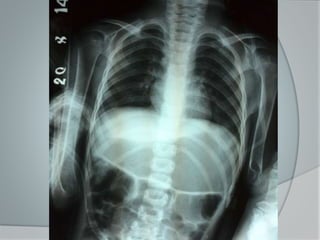

 1er semestre: En el cráneo

 2ndo semestre: Tórax

 Rosario Raquítico

 Hendidura De Harrison (El diafragma

tira de las costillas ablandadas durante

la inspiración)

Radiología

 Los cambios raquíticos se visualizan

con mayor facilidad en los Rayos X

posteroanteriores de muñeca.

 Disminución de la opacidad de las

metafisis. (imagen de doble contorno)

con una cortical que apenas destaca.

 (Nelson) metafisis de aspecto

deshilachado